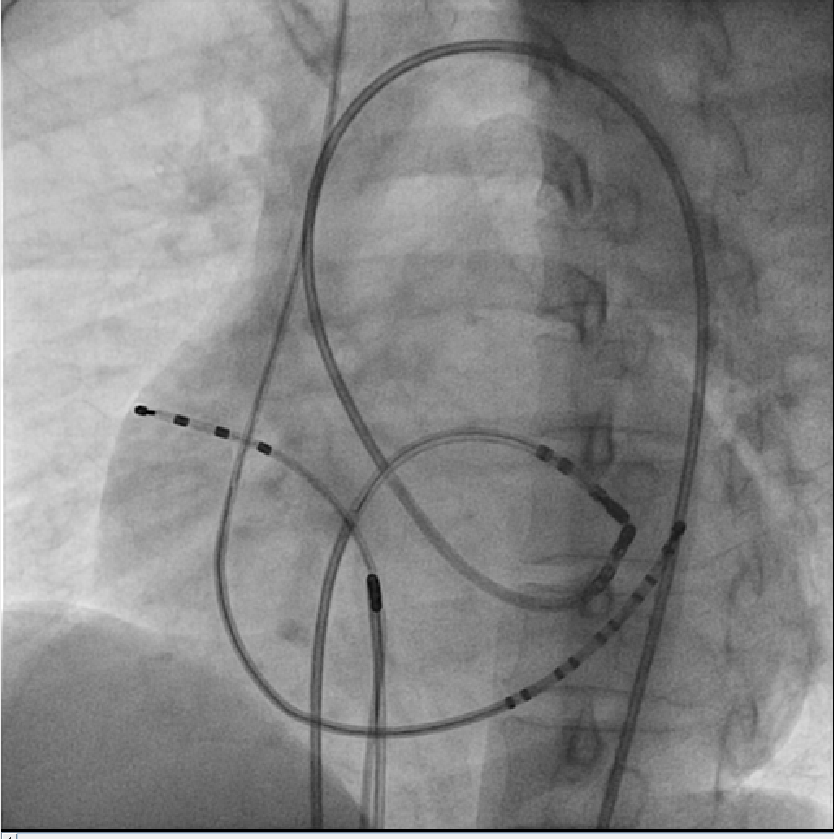

Stability

• Sheath

• Catheter course

• Retrograde approach

• Pacing if possible

• Entrain if during tachycardia